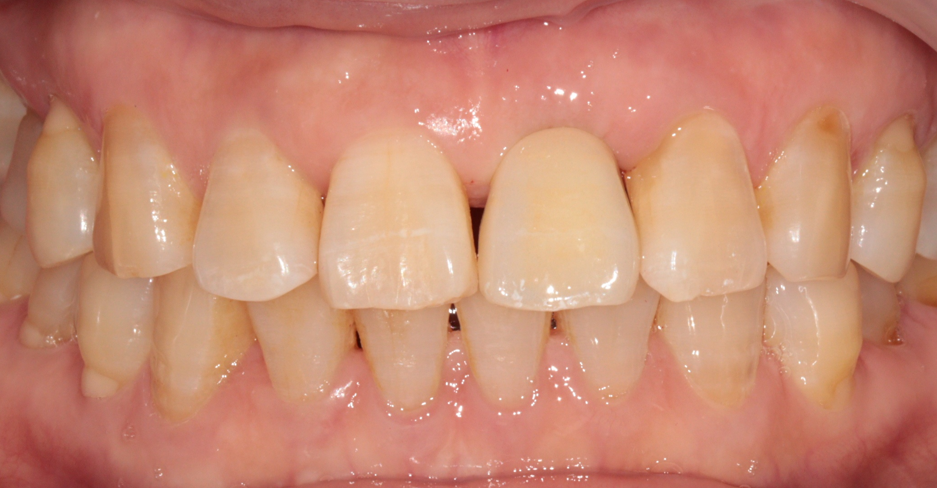

수술이 끝나자마자 미리 준비해둔 임시치아를 연결해드렸습니다.

이때 중요한 점은 수술한 임플란트에 바로 힘이 가해지면 안 된다는 것입니다.

그래서 임플란트 자체에 힘을 주는 방식이 아니라, 양옆의 튼튼한 인접 치아에 임시치아를 고정하는 방식으로 진행했습니다.

덕분에 수술 부위는 보호하면서도, 겉으로 보기에는 감쪽같이 치아가 있는 상태로 귀가하실 수 있었습니다.

환자분께서도 거울을 보시고 정말 안심하셨던 기억이 납니다.